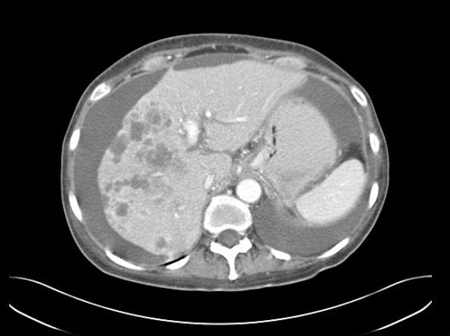

Adenocarcinoma of unknown primary site

CT abdomen with intravenous contrast, revealing numerous enhancing lesions in right hepatic lobe, with associated ascites; percutaneous biopsy of one of these lesions revealed adenocarcinoma, but no primary site was identified during routine work-up: a typical presentation of ACUP

From the personal collection of Dr D. Cosgrove